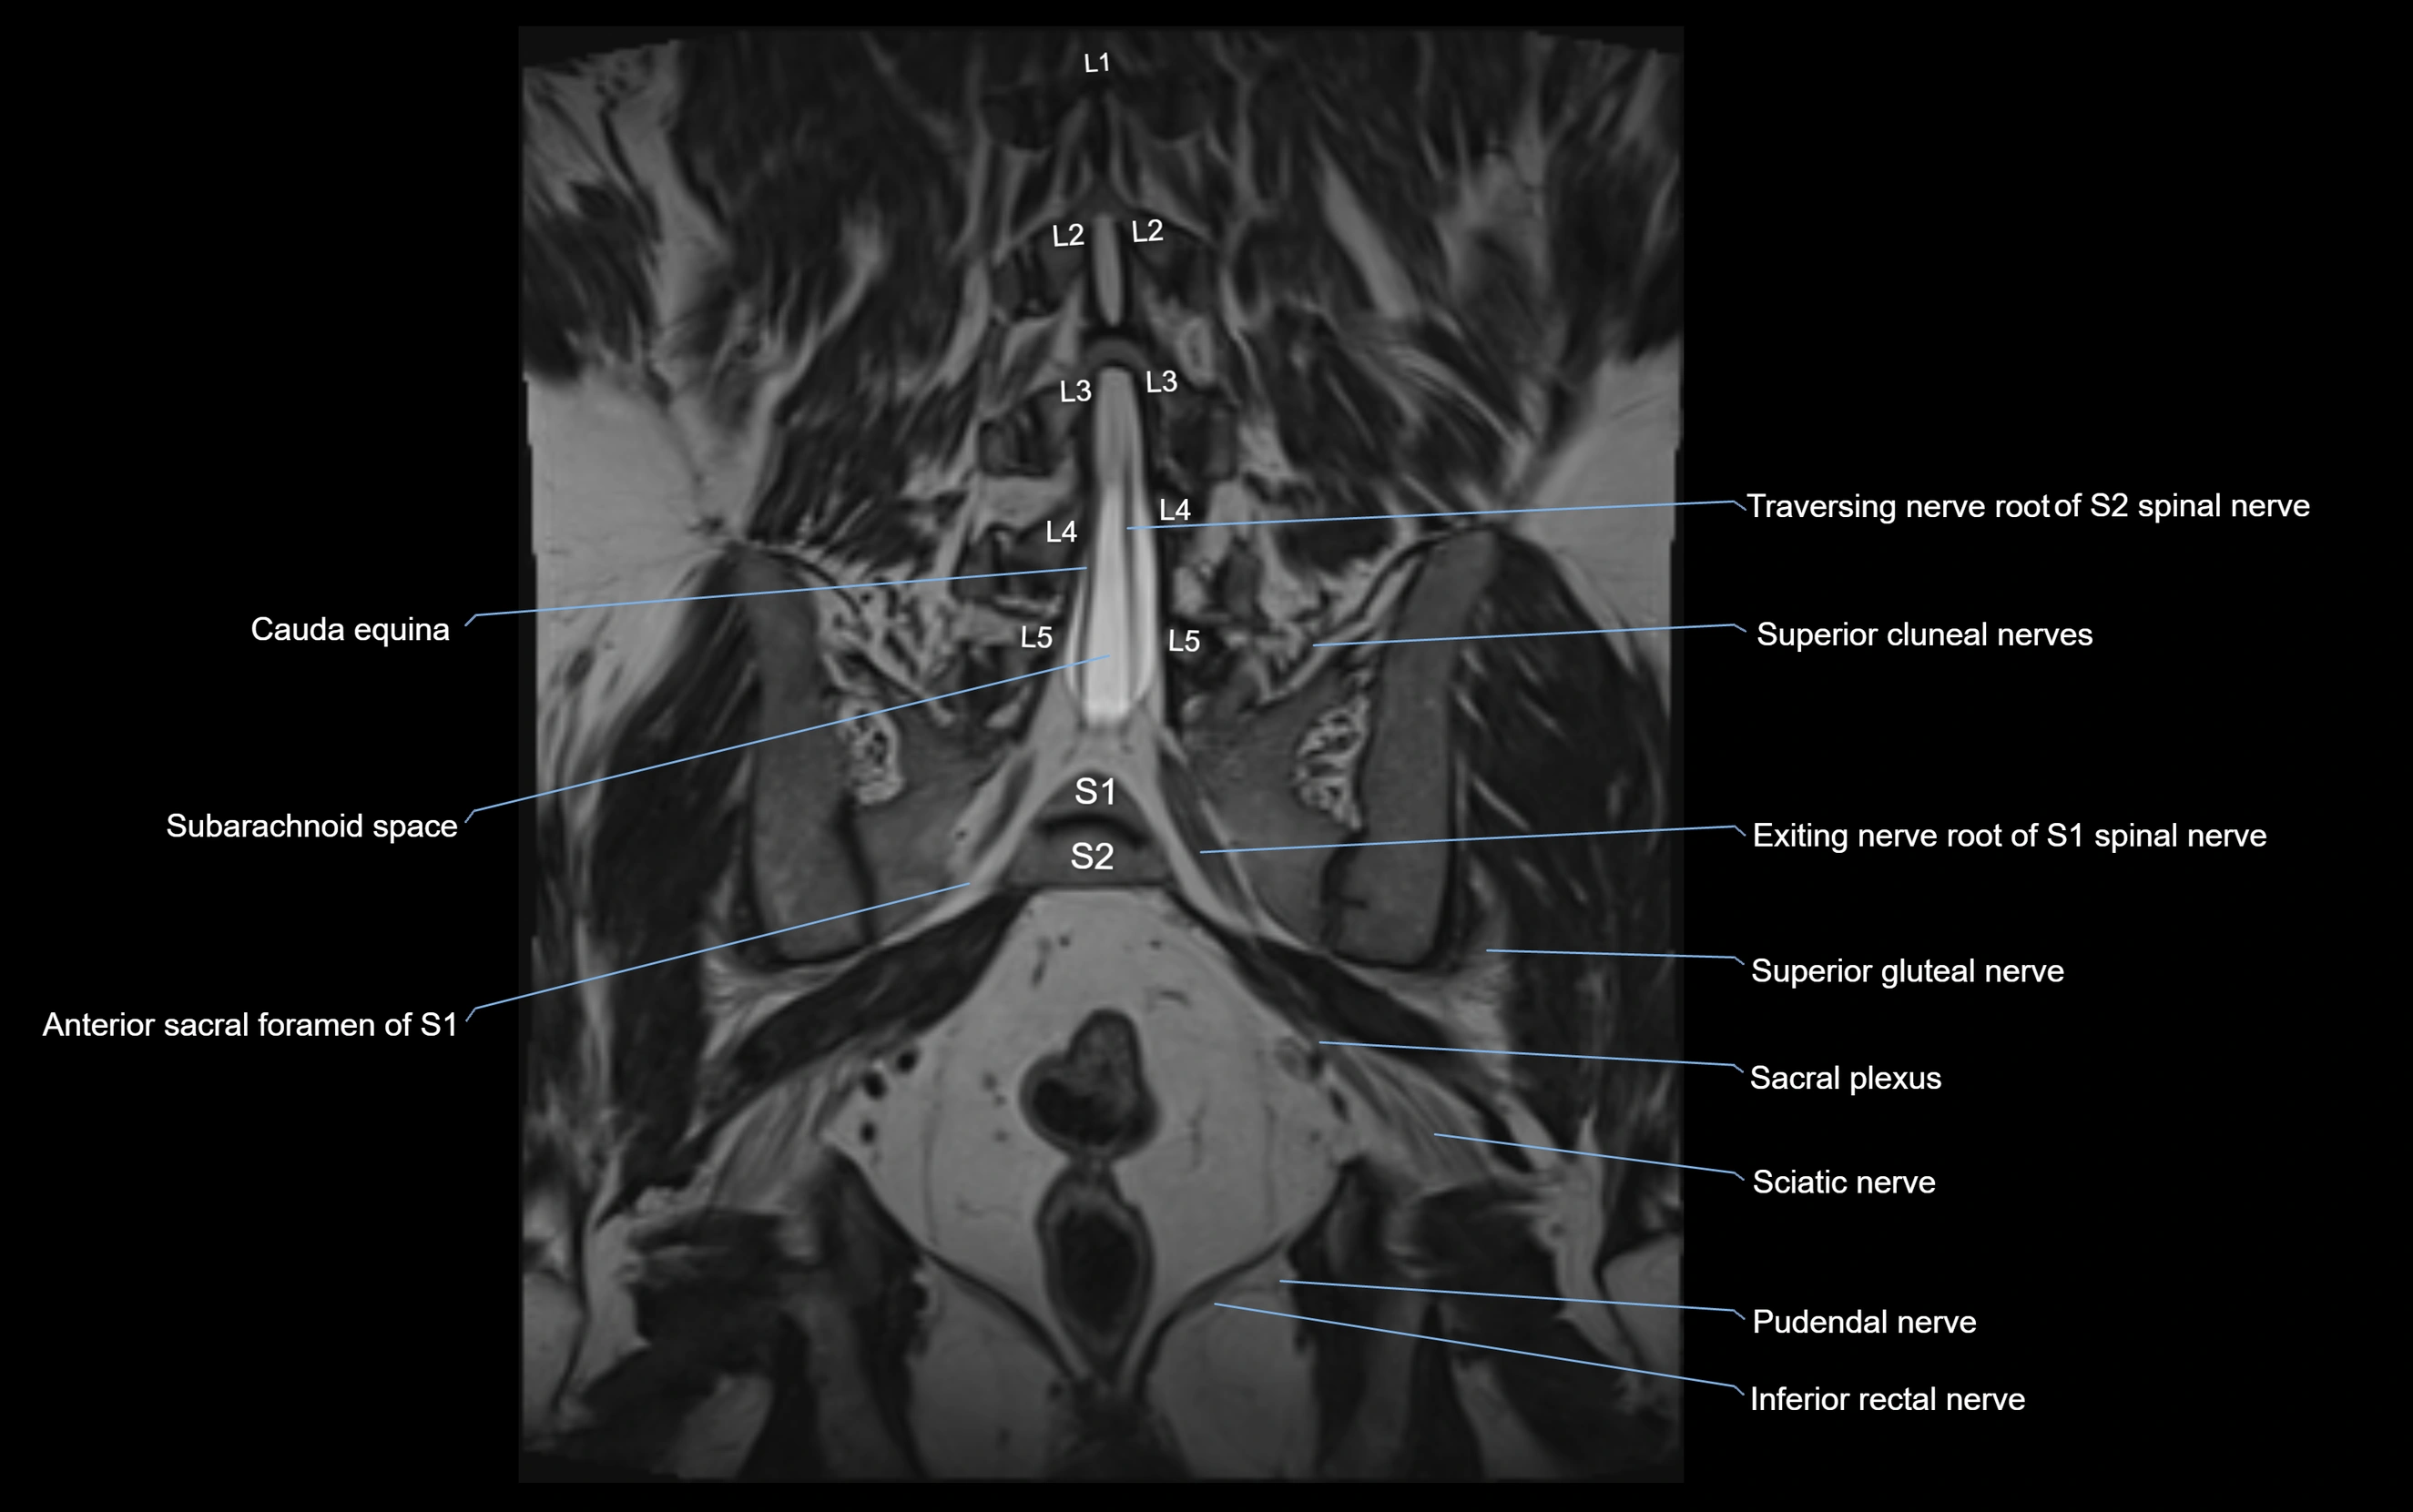

MRI Appearance

T1-weighted images:

• Nerve appears as a very thin low-to-intermediate signal intensity structure

• Surrounded by bright fat, aiding visualization

T2-weighted images:

• Nerve shows intermediate to mildly hyperintense signal compared to muscle

• Pathological involvement appears brighter

STIR (Short Tau Inversion Recovery):

• Normal nerve appears dark

• Inflamed or entrapped nerve appears bright hyperintense

T1 Fat-Sat Post-Contrast:

• Normal nerve enhances minimally

• Pathologic nerve (neuritis, entrapment, tumor infiltration) shows focal or diffuse enhancement

3D T2 SPACE / CISS:

• Nerve appears intermediate to mildly hyperintense compared to muscle

• Surrounded by bright fat or CSF, improving visualization

• Best sequence for mapping small pelvic nerves such as the anococcygeal